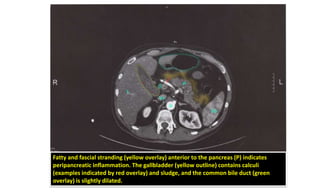

Fatty and fascial stranding (yellow overlay) anterior to the pancreas (P) indicates

peripancreatic inflammation. The gallbladder (yellow outline) contains calculi

(examples indicated by red overlay) and sludge, and the common bile duct (green

overlay) is slightly dilated.

Diagnosis: Imaging • CTscan: not routinely indicated – Findings: • Enlargement of the pancreatic parenchyma with edema; indistinct pancreatic margins with surrounding fat stranding • Necrotizing pancreatitis: lack of parenchymal enhancement or presence of air in the pancreatic tissue • Pancreatic abscess: circumscribed fluid collection

Fatty and fascialstranding (yellow overlay) anterior to the pancreas (P) indicates peripancreatic inflammation. The gallbladder (yellow outline) contains calculi (examples indicated by red overlay) and sludge, and the common bile duct (green overlay) is slightly dilated.